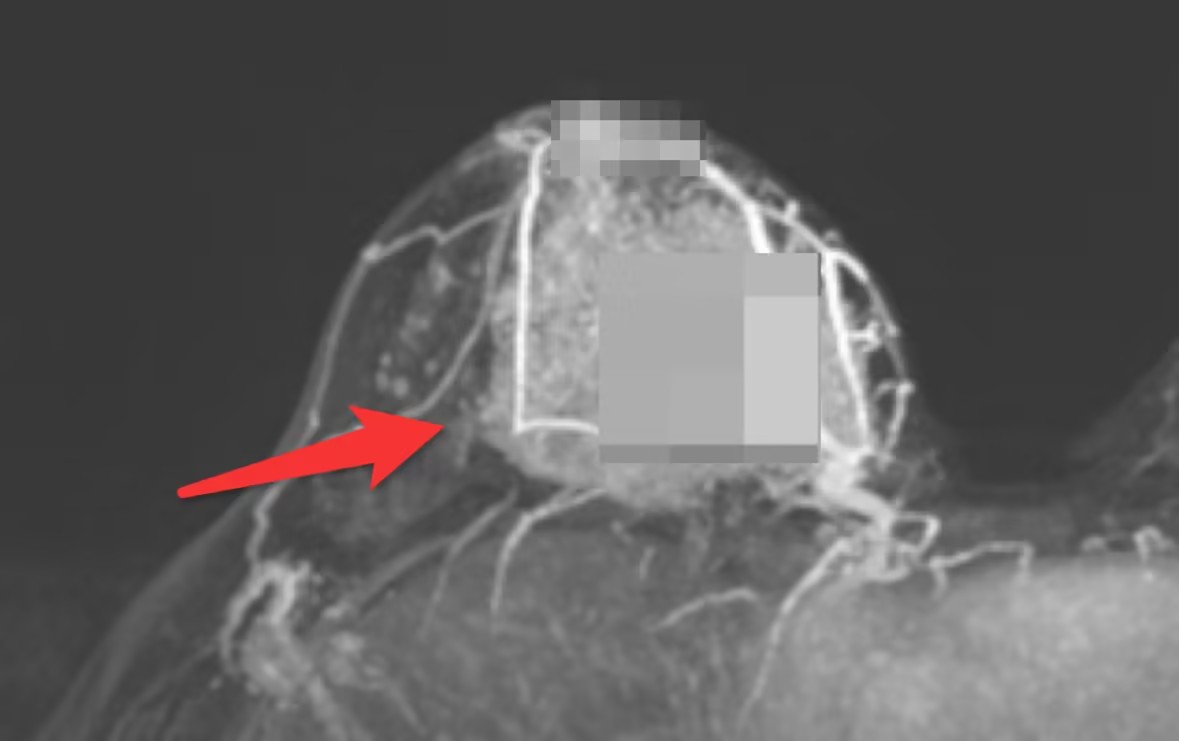

乳腺磁共振下巨大肿物穿刺提示为恶性